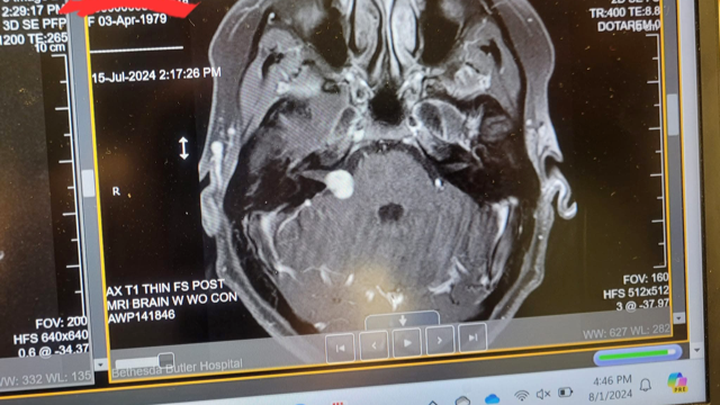

This fundraiser is for Rachel Reeves and Family. As many of you know, Rachel, has had some serious medical procedures and a difficult recovery that has left her back in the hospital. She needed brain surgery to remove a benign tumor. The surgery has caused facial paralysis and swelling. In addition, Rachel, has come down with Meningitis. Rachel is a wonderful mom and friend. Please consider donating to help ease the burden and stress of this difficult time. Her recovery is being estimated out 3 months and she will not be able to

work during that time.